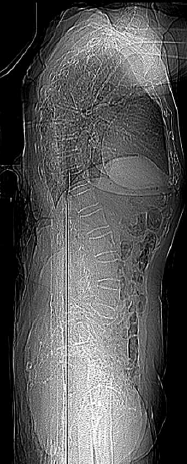

Paciente de 92 anos, sexo feminino, de forma abrupta e sem fator desencadeante, passou a sentir forte dor lombar que piorava à movimentação. A partir de então, deixou de caminhar devido à dor. Realizou uma radiografia de coluna lombar:

Enunciado 4100089-1

(Arquivo pessoal; imagem usada com autorização)

Diante desse achado, assinale a alternativa que apresenta o diagnóstico correto.